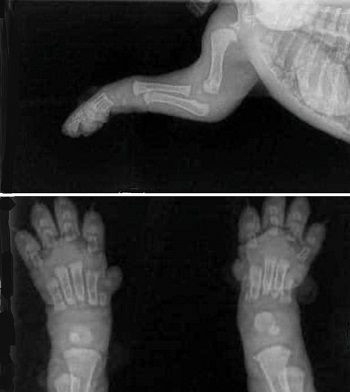

The most controversial aspects of both procedures are the consequences they have to the cavaliers' physical growth, behavioral issues, and future obesity and urinary incontinence. Spaying and neurtering do not just remove the dogs' sexually abilities, but also hormones essential to their growth. As an example, cavalier puppies are born without connective tissues -- joints and cartilage -- between their weight-bearing bones. (See x-rays at right.) As they mature, the bones continue to grow, and the cartilage and joints form and connect to those bones. Hormones in the dogs' sexual organs are instrumental in regulating that growth, and the premature removal of the sources of those hormones have been found to disrupt growth-plate closures (see chart below) and result in joint disorders and failure to appropriately end bone growth cycles.